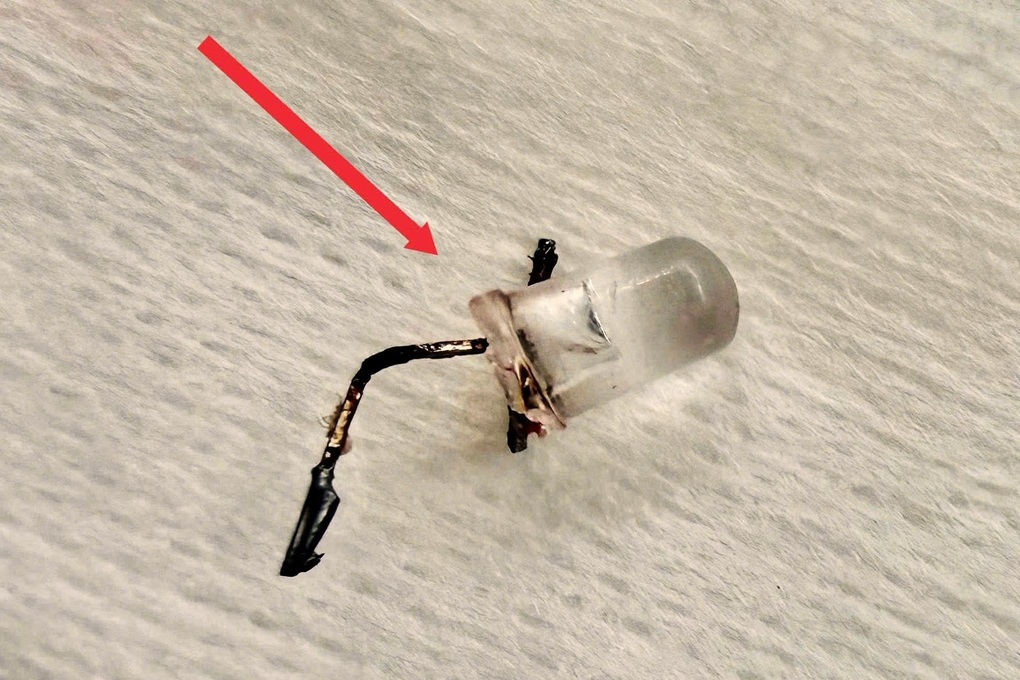

Dị vật nghi ngờ là một bóng đèn LED nằm sâu trong phế quản. Nhưng để lấy dị vật ra không hề dễ dàng. Khó khăn lớn nhất nằm ở cấu trúc của bóng đèn LED, vì phần đuôi đèn phình to và sắc nhọn, dễ mắc kẹt lúc kéo qua thanh quản, khiến nguy cơ gây trầy xước, rách niêm mạc hoặc kẹt lại ngay giữa 2 dây thanh là rất cao.

Bằng thao tác đúng chuyên môn, sự tỉ mỉ xoay trở từng milimet để lấy dị vật trong phế quản rất bé, cùng sự phối hợp chặt chẽ của đội ngũ y bác sĩ liên chuyên khoa, bóng đèn LED mắc kẹt cuối cùng đã được ê-kíp lấy ra an toàn khỏi cơ thể bệnh nhi.

Theo BSCKI Lý Phạm Hoàng Vinh, dị vật đường thở ở trẻ nhỏ luôn là cấp cứu nguy hiểm, đặc biệt với các vật có hình dạng bất thường như bóng đèn LED. Không chỉ gây tắc nghẽn, những dị vật này còn có thể gây trầy xước, thủng đường thở hoặc dẫn đến các biến chứng nặng nề nếu xử trí không đúng cách.